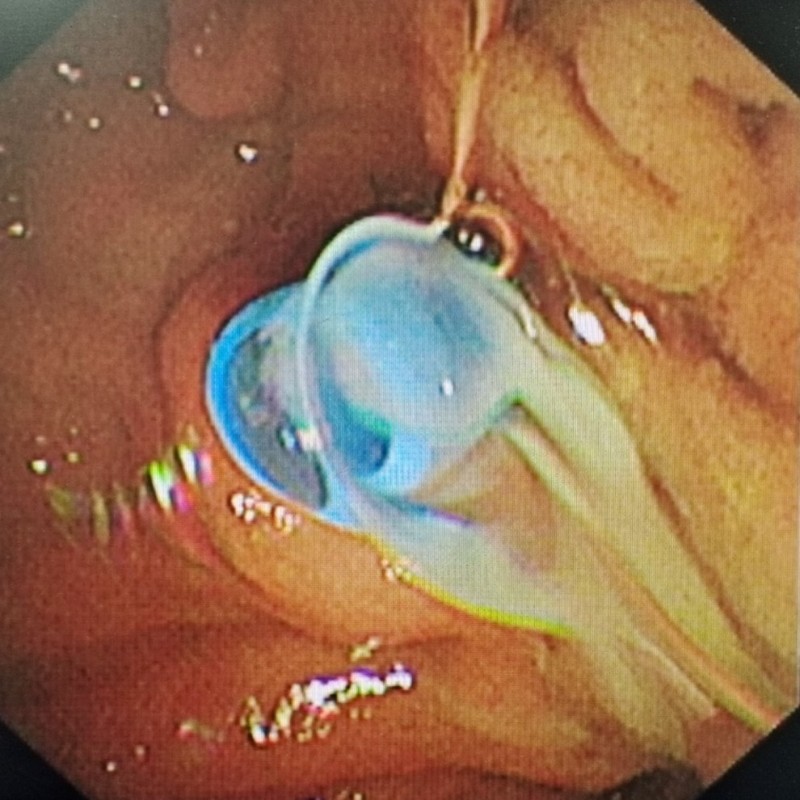

X造影见胆总管中下段狭窄 支架植入后见脓液流出

入院次日,在麻醉团队、内镜中心护士长曹琳琳及主管护师戴文帝的紧密协作下,陈新孚和副主任医师陈卓团队成功为李先生实施了ERC+内镜下胆管支架置入术+胆管冲洗术。术中,胆管支架的植入有效缓解了梗阻症状,大量脓液被引流而出,李先生的状况迅速好转。